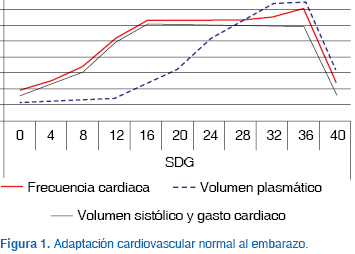

Sistema cardiovascular: El aumento del volumen plasmático es el cambio más importante que se presenta durante el embarazo, alcanza un incremento del 30% a las 32 semanas y después de la semana 37 se incrementa hasta un 50%4,7-10 (Figura 1).

El volumen sistólico aumenta de manera temprana en el embarazo y luego disminuye hasta niveles pregrávidos en el último trimestre. Incrementos en los estrógenos plasmáticos con la consecuente estimulación en receptores miocárdicos alfa resultan con aumentos de frecuencia cardiaca de 10 a 20 latidos por minuto, causando por este mecanismo un incremento en el gasto cardiaco desde las semanas 8 a 10 de gestación, con picos en las semanas 25 a 304,7-10 (Figura 1). El crecimiento auricular y el aumento de estrógeno en el embarazo disminuyen el umbral para las arritmias.7 Por otro lado, el volumen de los eritrocitos aumenta en el embarazo de término hasta en un 18%. Este aumento es menor en magnitud que el aumento en el volumen plasmático y genera la llamada anemia fisiológica del embarazo, con valores de hematócrito entre 30-33% para el final del embarazo.8,9,11